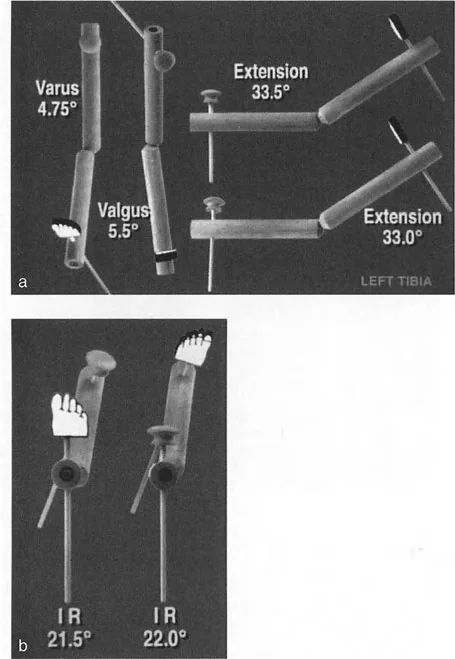

الشكل 12-29أ، ب: الاختلافات في القياسات الإسقاطية الناتجة عن منظورين مرجعيين مختلفين (المتطابقات المنظرية). في المنظر الأمامي الخلفي بالنسبة للقطعة المرجعية الأمامية للركبة، تبدو الساق بـ 4.75 درجة من التقوس للداخل. أما بالنسبة للقطعة المرجعية الأمامية للقدم، فتبدو بـ 5.5 درجة من التقوس للخارج. تختلف قياسات الدوران أيضًا بناءً على منظور المراقب.